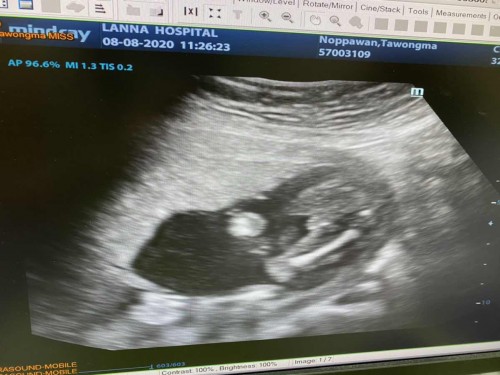

เพศ

เด็กชายจ้า 4เดือนโชว์ของแล้ว

เห็นตั้งแต่ 13 วีค 5555 ชัดมาเลยครับลูก